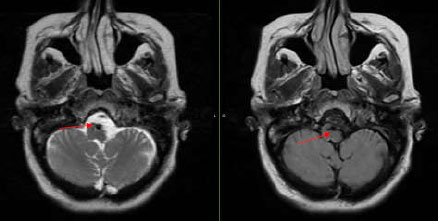

The patient, who presented with transient episodes of focal neurological deficits for six months, is a Caucasian female in her late 50s with a medical history of Hypertension and Diabetes. These episodes were wake-up weakness, confusion, and dysarthria on the right side of the body. She was prescribed Aspirin by a local neurologist. The episodes became more severe as she would have transient quadriparesis, dizziness, and aphasia lasting for several hours. These symptoms would happen particularly in the right lateral position. Her neurological exam was completely normal. CT scan head was normal, while CT Angiography revealed increased tortuosity of the V4 segments of the vertebral arteries and the basilar artery. These were indenting the Medulla oblongata. MRI brain confirmed similar findings (Fig. 1). A conventional angiogram was done, which revealed compression of the medullary pyramid on the left side due to dilated proximal basilar artery associated with significant vertebrobasilar atherosclerotic plaques (Fig. 2). No rate-limiting changes in flow were observed while turning the head to either side during the procedure, but approximately 50% flow arrest was seen in the right vertebral artery on turning the patient’s head to the right.